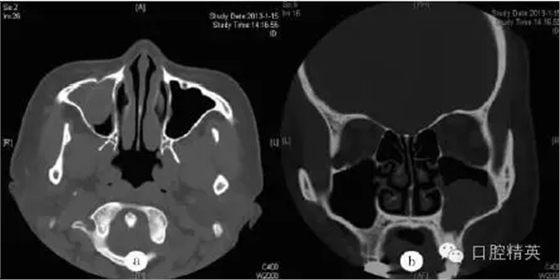

鼻竇CT檢查示:右側(cè)尖牙牙根處有一類圓形軟組織密度影(圖a),病變向上進(jìn)入右側(cè)上頜竇,其內(nèi)見弧形線狀高密度影,鄰近牙槽骨壓迫性骨吸收(圖b)??紤]為根尖囊腫并發(fā)感染(右)。

圖a:術(shù)前水平位CT檢查顯示右側(cè)上頜竇黏膜囊腫,中央有類圓形影;圖b:術(shù)前冠狀位CT檢查顯示右側(cè)上頜竇黏膜囊腫并根尖骨質(zhì)吸收,含類圓形影;